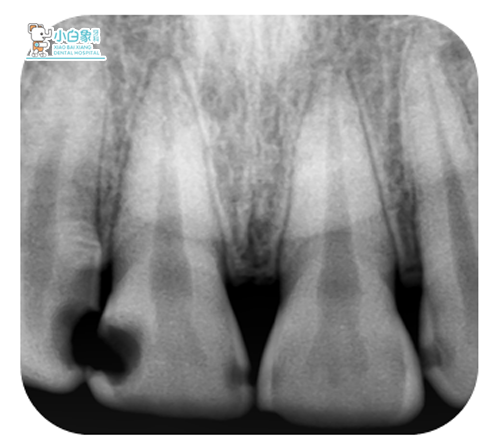

X线检查:11远中低密度暗影达髓腔,12近中低密度暗影近髓,根尖未见明显异常。

诊断:色素沉着;11牙髓炎;12深龋;21牙体缺损。